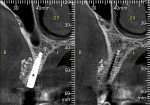

A 69-year-old female patient presented with a request for implants to replace the posterior left mandibular teeth that had been missing for several years. A CBCT was taken and cross-sections were analyzed in planning for implant placement. Adequate width was noted mesial to the mental foramen, but inadequate width was revealed distal to the mental foramen (Figure 11). The area was flapped and two implants were placed mesial to the mental foramen. A surgical bur was used to perforate the lateral aspect of the ridge distal to the mental foramen to create bleeding points (Figure 12). Bond Apatite was mixed and placed over the previously perforated bone and over the implants that had just been placed (Figure 13).

Following 4 months of healing to allow the graft to mature and organize, a CBCT was taken. Cross-sectional slices demonstrated a ridge width increase in the area distal to the mental foramen that would allow implant placement (Figure 14). The area was flapped, osteotomies were prepared, and implants were placed (Figure 15).